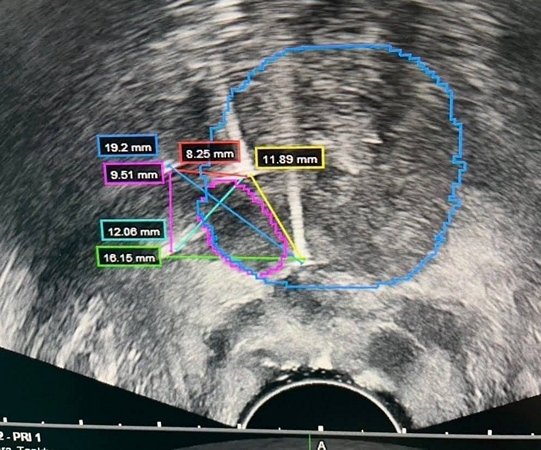

ร.พ.สมเด็จพระนางเจ้าสิริกิติ์ กรมแพทย์ทหารเริอ อ.สัตหีบ จ.ชลบุรี ได้ดำเนินการรักษาผู้ป่วยด้วยเทคนิค IRE (Irreversible Electroporation) Focal Prostate Therapy เป็นรายแรก สำเร็จลุล่วง เมื่อวันที่ 5 เม.ย.69 นับเป็นอีกหนึ่งความก้าวหน้าทางการแพทย์ที่มุ่งเน้นการรักษาแบบจำเพาะจุด (Focal Therapy) เพื่อลดผลกระทบต่อเนื้อเยื่อข้างเคียง และคงคุณภาพชีวิตของผู้ป่วยให้ได้มากที่สุด

IRE เป็นนวัตกรรมการรักษาที่ใช้กระแสไฟฟ้าความเข้มสูงในการทำลายเซลล์มะเร็งเฉพาะบริเวณเป้าหมาย โดยไม่ก่อให้เกิดความร้อนสูง จึงช่วยลดความเสียหายต่อโครงสร้างสำคัญ เช่น เส้นประสาทและหลอดเลือดบริเวณรอบข้าง ส่งผลให้ลดภาวะแทรกซ้อน เช่น ภาวะกลั้นปัสสาวะไม่ได้